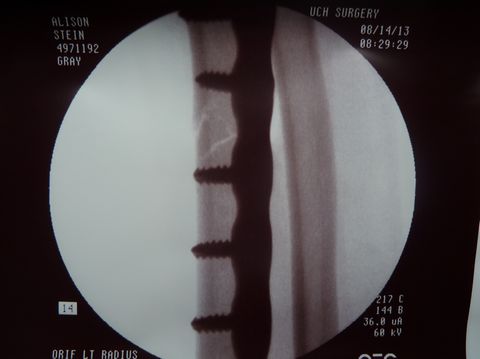

He fitted the margins perfectly back into place, laid a

plate into position, drilled a few holes, and screwed the plate

onto the bone.![]() |

Dr. Gray used flouroscopy to confirm that the fracture margins were in perfect alignment, secured by three screws proximal and three screws distal to the fracture. |

| In fact, one view (below right) shows such tight apposition and such perfect alignment, that one cannot even see the fracture margins. | |